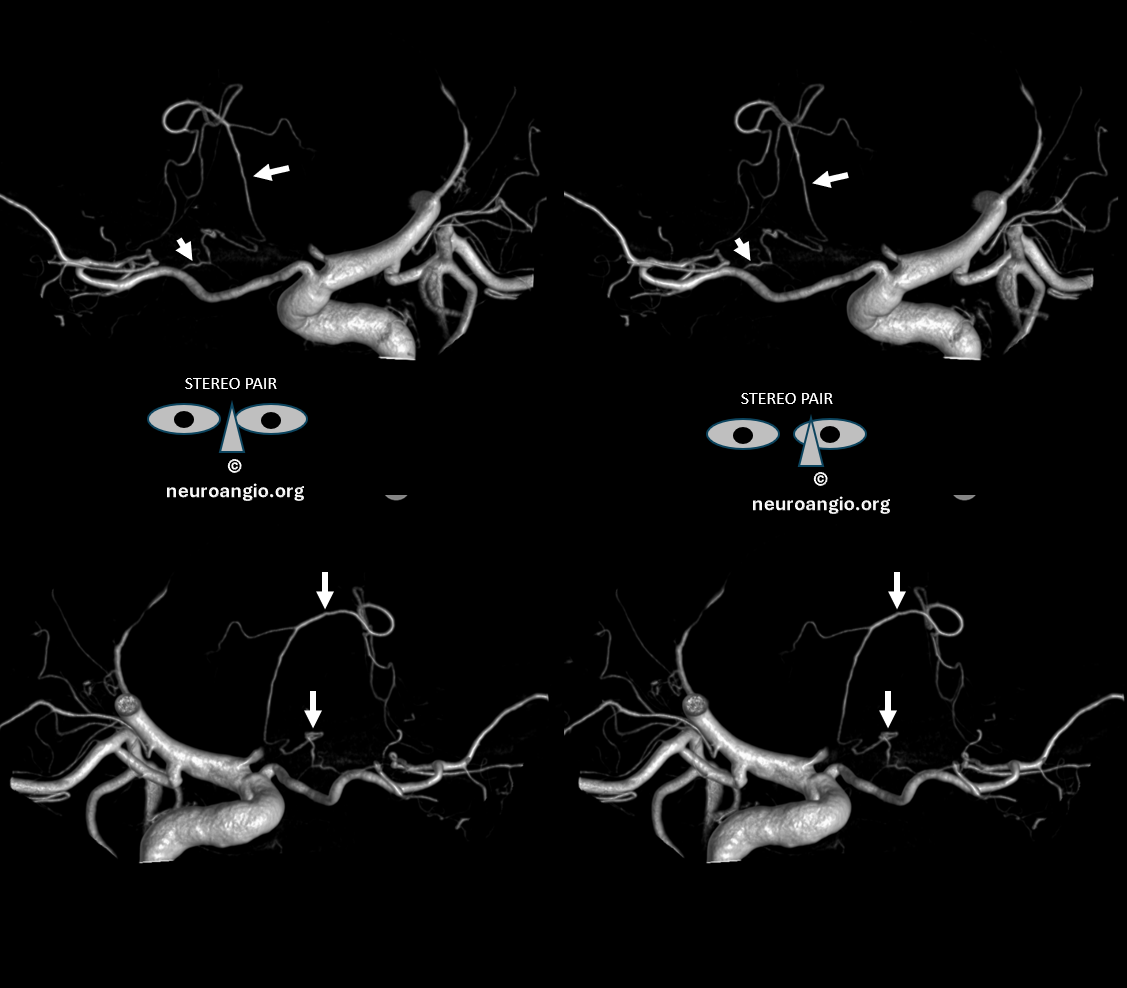

Stereo Pair volume rendered images

with arrows